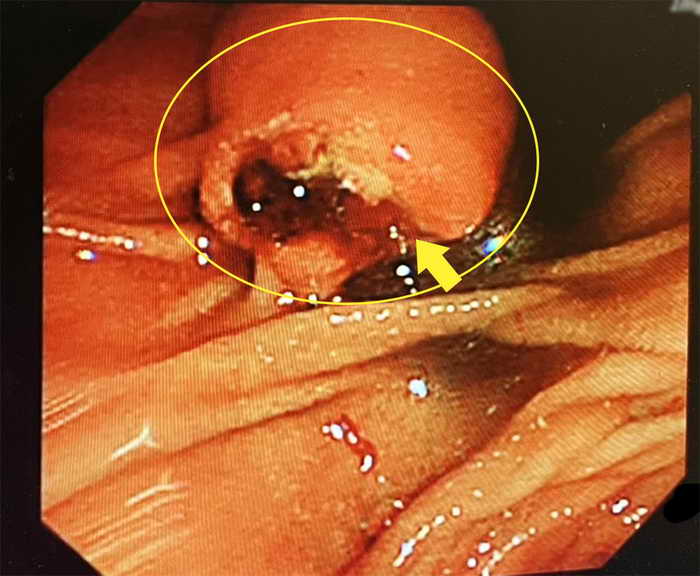

何士奇立即安排患者內視鏡檢查,確認十二指腸的壺腹部有一顆約1.5公分腫瘤,經切片診斷為惡性,需採取手術切除以根除治癒。

何士奇說明,壺腹是膽管胰管與十二指腸交會樞紐,結構相對複雜,在早期無明顯症狀時較不容易被發現,而壺腹癌是罕見的癌別,在臺灣每年約有100人罹患壺腹癌,如晚期發現無法手術時,5年存活率僅剩不到3成,因為該患者進行超音波檢查,才能在第一時間察覺異樣,而除了腹部超音波,也可以透過電腦斷層、核磁共振或是抽血檢驗發現。

圖二:45歲男經內視鏡檢查罹患罕見壺腹癌。